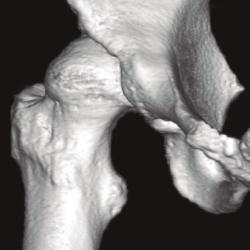

Radiológicamente, estos pacientes en los que podría considerarse un manejo artroscópico se engloban en la displasia de tipo A de Hartofilakidis. Debemos realizar radiología simple anteroposterior de pelvis, axial de Dunn, lateral pura y la proyección de falso perfil de Lequesne. Los ángulos a evaluar serían, de forma básica, el ángulo de inclinación acetabular (IA) o de Tönnis, así como el ángulo centro-borde lateral (CBL) o de Wiberg (Figura 5). En general, el ángulo de IA debe ser menor de 10°, mientras que el ángulo CBL debe ser mayor de 25°.

Figura 5. Medición de los ángulos centro-borde lateral, de 18,1° (Wiberg), y de inclinación acetabular, de 13,5° (Tönnis).

Respecto a las pruebas diagnósticas necesarias para evaluar a estos pacientes, la radiología simple con anteroposterior de pelvis y axial de caderas se postula como la base de las pruebas diagnósticas para la medición de los ángulos de cobertura. El falso perfil de Lequesne se debe realizar sistemáticamente para valorar la cobertura anterior. La realización de artro-RM es la mejor alternativa para la evaluación del labrum y la unión condrolabral, donde suelen verse en estos pacientes quistes paralabrales. Especialmente importante es la realización de TC con reconstrucción 3D en aquellos pacientes con osteotomías femorales o acetabulares previas en la infancia (Figura 6). La valoración de la anteversión femoral es muy importante y debe medirse con TC o resonancia realizando cortes al nivel de los cóndilos femorales.

Figura 6. Reconstrucción 3D de tomografía computarizada en displasia de cadera con descobertura anterior.